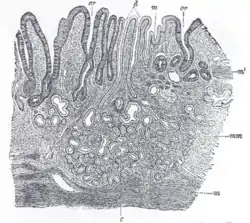

![]() Section of mucous membrane of human stomach, near the cardiac orifice. X 45. c. Cardiac glands. d. Their ducts. cr. Gland similar to the intestinal glands, with goblet cells. mm. Mucous membrane. m. Muscularis mucosæ. m’. Muscular tissue within the mucous membrane. | |

The gastric mucosa is the mucous membrane layer of the stomach, which contains the glands and the gastric pits. In humans, it is about 1 mm thick, and its surface is smooth, soft, and velvety. It consists of simple columnar epithelium, lamina propria, and the muscularis mucosae.

When examined with a lens, the inner surface of the mucous membrane presents a peculiar honeycomb appearance from being covered with funnel-like depressions or foveolae of a polygonal or hexagonal form, which vary from 0.12 to 0.25 mm. in diameter. These are the ducts of the gastric glands, and at the bottom of each may be seen one or more minute orifices, the openings of the gland tubes. Gastric glands are simple or branched tubular glands that emerge on the deeper part of the gastric foveola, inside the gastric areas and outlined by the folds of the mucosa.

The surface of the mucous membrane is covered by a single layer of columnar epithelium. This epithelium commences very abruptly at the cardiac orifice, where there is a sudden transition from the stratified epithelium of the esophagus. The epithelial lining of the gland ducts is of the same character and is continuous with the general epithelial lining of the stomach. An important iodine concentration by sodium-iodide symporter (NIS) is present in mucinous cells of surface epithelium and gastric pits of the fundus and pyloric part of the stomach.[1][2]